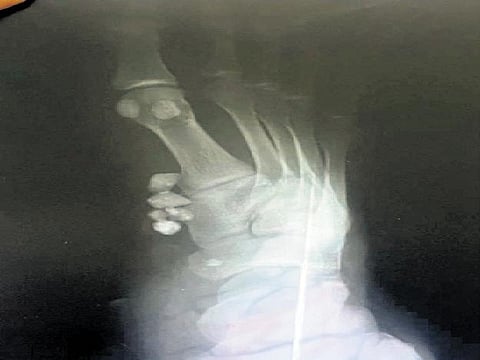

After getting the wounds cleaned and stitched, Mathivanan left the hospital. However, with the affected leg developing pain despite treatment, he consulted a private hospital in Aranthangi on Saturday. X-rays taken there revealed stones inside the leg, near to the wounded patch, Mathivanan said, and alleged the general hospital in Aranthangi of negligence for stitching the wound without removing the stones.

"The private hospital staff told me that the stones may affect the entire leg if not removed in time," Mathivanan said. Subsequently, all the stones were successfully taken out from the leg, sources said. The news about the incident swiftly spread across the locality, leading to public outrage, sources said.